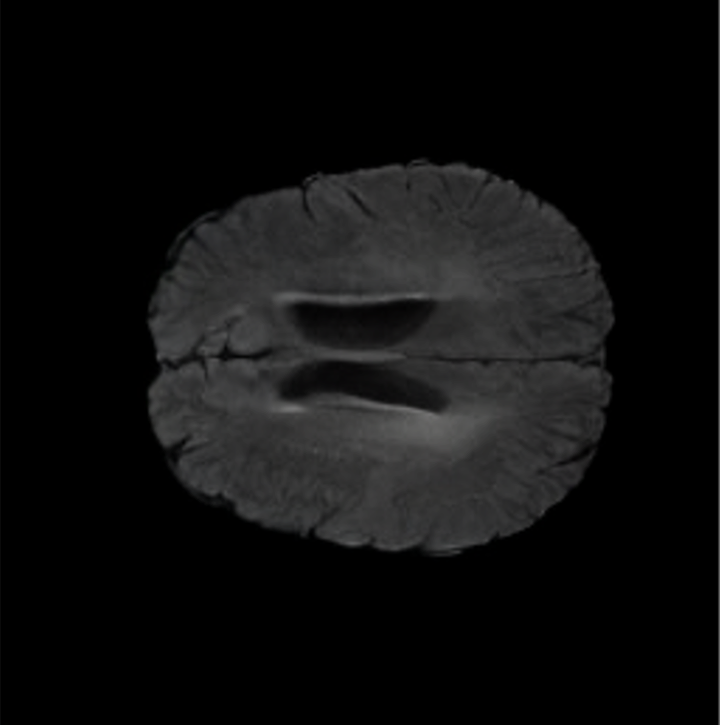

UK Biobank. A more comprehensive dataset of 48,384 full-body MRIs from more than 500,000 volunteers[67], capturing diverse physiological attributes across a broad demographic spectrum. These Dixon MRIs do not come stitched, the scans are scanned axially and there is a disparity in the bias field effect (a common artifact of MRI machines) which is strongest at the knee region. The same knee pattern is present on all samples in the dataset. UK Biobank MRIs are resampled to be isotropic and cropped to a consistent resolution (501 160 224). 48,384 whole-body MRIs are paired with antero-posterior (AP) DXA scans of the same subjects.

Notably, X-Diffusion achieves state-of-the-art dB for a few input slices while baselines require more than 60 input slices to achieve similar performance (Figure 7). The margin is more than 12 dB PSNR for the 1-slice input in both the BRATS and the UK Biobank benchmarks (see Table 1 and Figure 6). For reference, two randomly sampled MRIs from UK Biobank would have a PSNR of 15.95 dB 0.36 (on 4800 randomly sampled examples). Omitting the preprocessing step of alignment DXA to MRI, leads to a drop of PSNR on average by 2.87 dB (29.01 dB 26.14 dB). The slices from 3D reconstructed volumes at varying depths and axis of rotation, visually match the ground truths for both brain and whole-body scans (see Figures 4 and 5 left). We also plot the error map (Figure 3) and the spread of the error (Figure 5 right) of such X-Diffusion generations to highlight the differences with the ground truth MRIs.